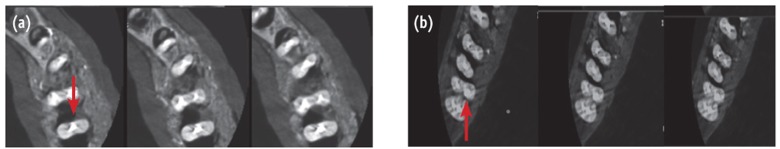

CBCT images were obtained using Cranex 3D (Soredex) in an upright position. The mandibles were fixed in a chin rest similar to the location of the patient's jaw. Radiation was emitted at high-resolution mode with 90 kVp, 4 mA, 12.6 seconds, voxel size of 0.2 × 0.2 × 0.2 mm, field of view of 6 × 8 cm and 0.2 mm slice thickness. The images were reconstructed at 0.2 mm intervals and stored in Digital Imaging and Communications in Medicine (DICOM) format (Figure 4). MDCT images were obtained using a Somatom Emotion 16 (Siemens, München, Germany) operated at 130 kVp and 80 mAs. The specimens were stabilized on the gantry, and axial scan images were adjusted parallel to the occlusal plane of the teeth. Images were obtained at a slice thickness of 0.75 mm and were reconstructed to 0.2 mm intervals and finally stored in DICOM format (Figure 5).

Metal artifacts related to radiopaque materials inside the canal decrease the accuracy of CBCT in detecting endodontic complications.12,24 According to Hassan et al., streak artifacts associated with root canal filling could mimic fracture and reduce the specificity of CBCT scans in diagnosis.25 The same artifact could increase the risk of perforation misdiagnosis. Bueno et al. suggested that sequential axial slices of 0.2 mm/0.2 mm of each root from coronal to apical (or from apical to coronal) could reduce the beam hardening effect associated with endodontic material by decreasing the amount of filling near the perforation location.26 This procedure provides precious information regarding the location of communication between the root canals and the periodontal space, hence suggesting root perforations. This strategy was used to allow better detection of perforations by CBCT.

CT scans of the jaws are primarily used for the temporomandibular joints and then for the three-dimensional reconstruction of the jaws before major maxillofacial operations, bone evaluation for implant placement, and detection of vertical root fractures.27,28,29,30 The authors did not find any reports on the diagnosis of root perforation with CT in the literature. MDCT had the lowest sensitivity in detecting perforations possibly due to the difference in spatial resolution.31 Spatial resolution of CI, PSP and CBCT were superior to that of MDCT (> 20 LP/mm, 6 - 8 LP/mm, and 3.1 LP/mm versus 2 LP/mm, respectively).16,17,31 However, superimposition of the neighboring structures reduces the sensitivity of PRs while the 3D nature of CBCT and MDCT allows visualization of the peroration in various sections and angulations.23 In our study, a slice thickness of 0.2 mm for CBCT and 0.75 mm for MDCT affected the spatial resolution of the reconstructed axial images of CBCT and MDCT.31,32 Several studies stated that for detailed evaluation of the mandible, it is essential to obtain CT scans with narrow cuts at bone windows, when the diameter of lesion is comparable to or less than the CT slice thickness, identification of the lesions is inaccurate.31,33 As a result, it is difficult to diagnose such small perforations with MDCT.